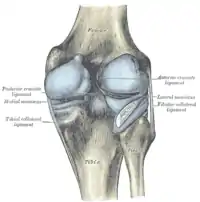

La rodilla está sustentada por fuertes ligamentos que impiden que sufra una luxación, siendo los más importantes el ligamento lateral externo, el ligamento lateral interno, el ligamento cruzado anterior y el ligamento cruzado posterior.[4]

Ligamentos

La rodilla esta sustentada por varios ligamentos que le dan estabilidad y evitan movimientos excesivos. Los ligamentos que están en el interior de la cápsula articular se llaman intraarticulares o intracapsulares, entre los que se encuentra el ligamento cruzado anterior y el ligamento cruzado posterior. Por otra parte los ligamentos que están por fuera de la cápsula articular se llaman extrarticulares o extracapsulares como el ligamento lateral interno y el ligamento lateral externo.[8][9]

Extrarticulares

- Cara anterior

- Ligamento rotuliano que une la rótula a la tibia.

- Cara posterior.

- Ligamento poplíteo oblicuo o tendón recurrente. Une el tendón del músculo semimembranoso al cóndilo externo del fémur.[9][12]

- Ligamento poplíteo arqueado. Une el cóndilo externo del fémur con la cabeza del peroné en la rodilla.[9]

- Cara interna

- Ligamento alar rotuliano interno. Une el borde de la rótula al cóndilo interno del fémur.

- Ligamento menisco rotuliano interno. Une la rótula al menisco interno.

- Ligamento lateral interno o ligamento colateral tibial.

- Cara externa

- Ligamento alar rotuliano externo. Une el borde de la rótula al cóndilo externo del fémur.

- Ligamento menisco rotuliano externo. Une la rótula al menisco externo.

- Ligamento lateral externo o ligamento colateral peroneo.